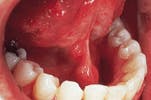

Case 3

Lymphangioma